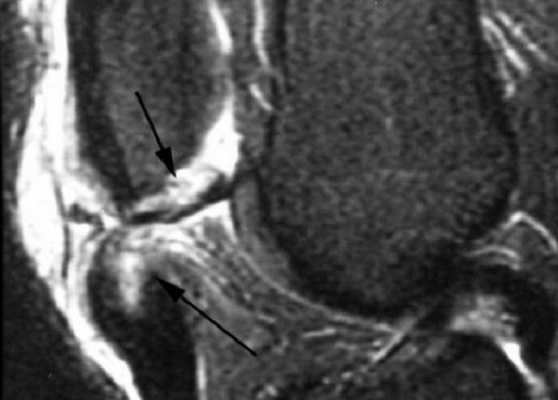

МРТ: перелом надколенника, разрыв сухожилия (стрелки)

Причины изменений структур сочленения вариативны, дисфункцию может вызвать: